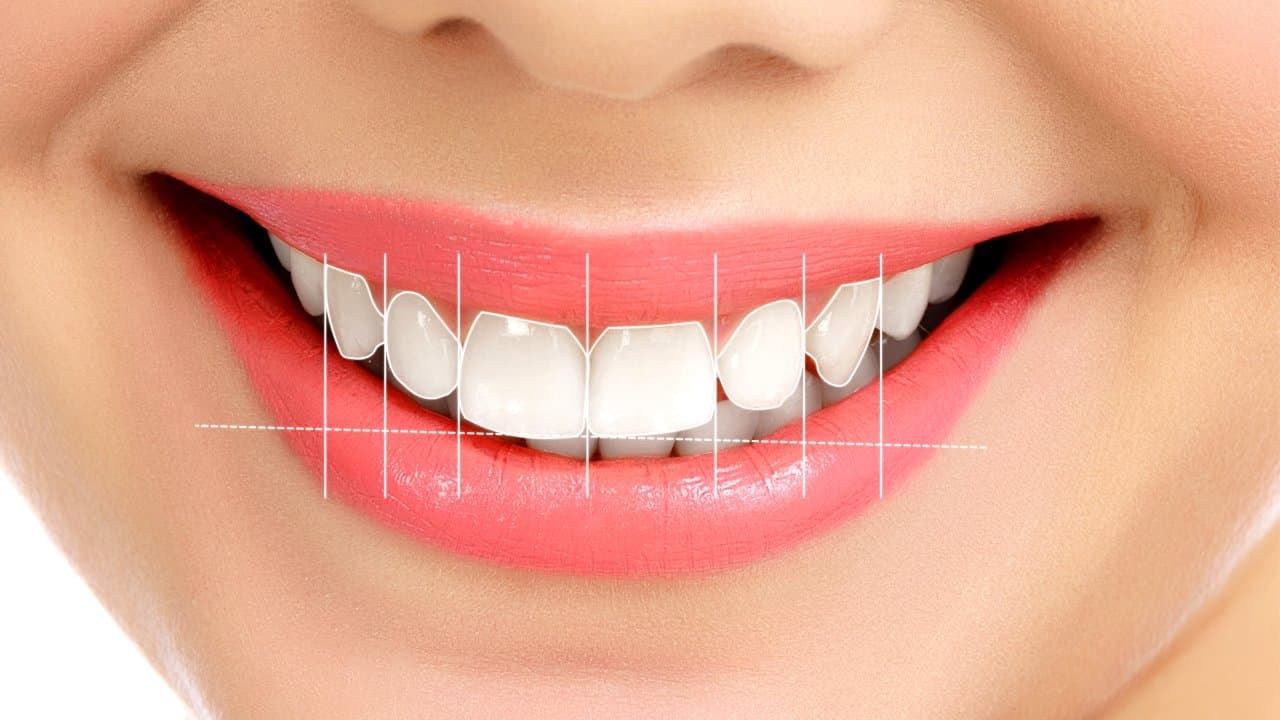

Şehrin en parlak gülüşleri burada tasarlaniyor

Dijital planlama, 3D tarama ve konfor odaklı tedavi protokolleriyle, diş hekimi deneyimini yeniden tasarlıyoruz.

Gülüşünüzün Tasarımında Yeni Dönem

hayalinizdeki gülüşe kavuşun. Kişiye özel, doğal ve kalıcı hizmetler